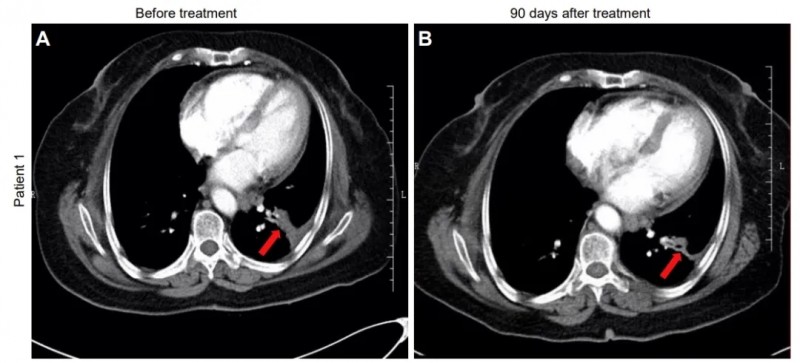

患者1:是一位68岁女性,患IVA期非小细胞肺癌(NSCLC),治疗前左肺下叶可见3.8×1.8×2.4cm片状肿瘤;治疗90天后CT显示肿瘤缩小至2.5×1.2×2.1cm(详见下图)。

▲图源“JCI”,版权归原作者所有,如无意中侵犯了知识产权,请联系我们删除